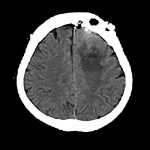

’12_13

'12年1月

70代

脳腫瘍

断層撮影

手術前1

No.’12_13 手術前1